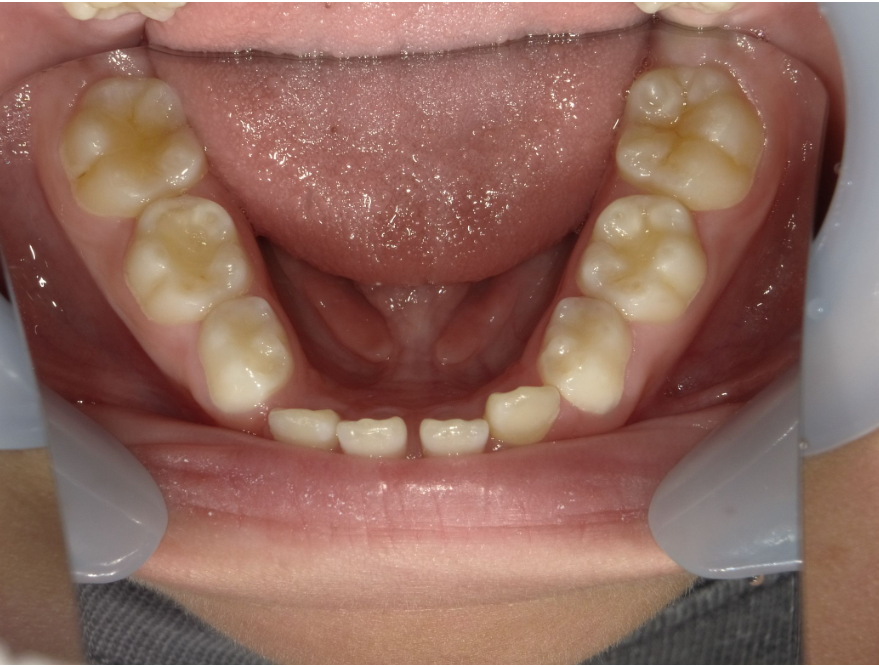

下顎

| 治療内容 | インビザライン・ファースト |

| 治療詳細 | スペース不足や交叉咬合を整えるために、歯の表面にアタッチメント(白い突起)をつけ、治療を行いました。 |

| 患者情報 | 9歳 男性 予防矯正から移行 |

| 主訴 | 永久歯は生えそろう十分なスペースがない 一部分だけかみ合わせが反対 |